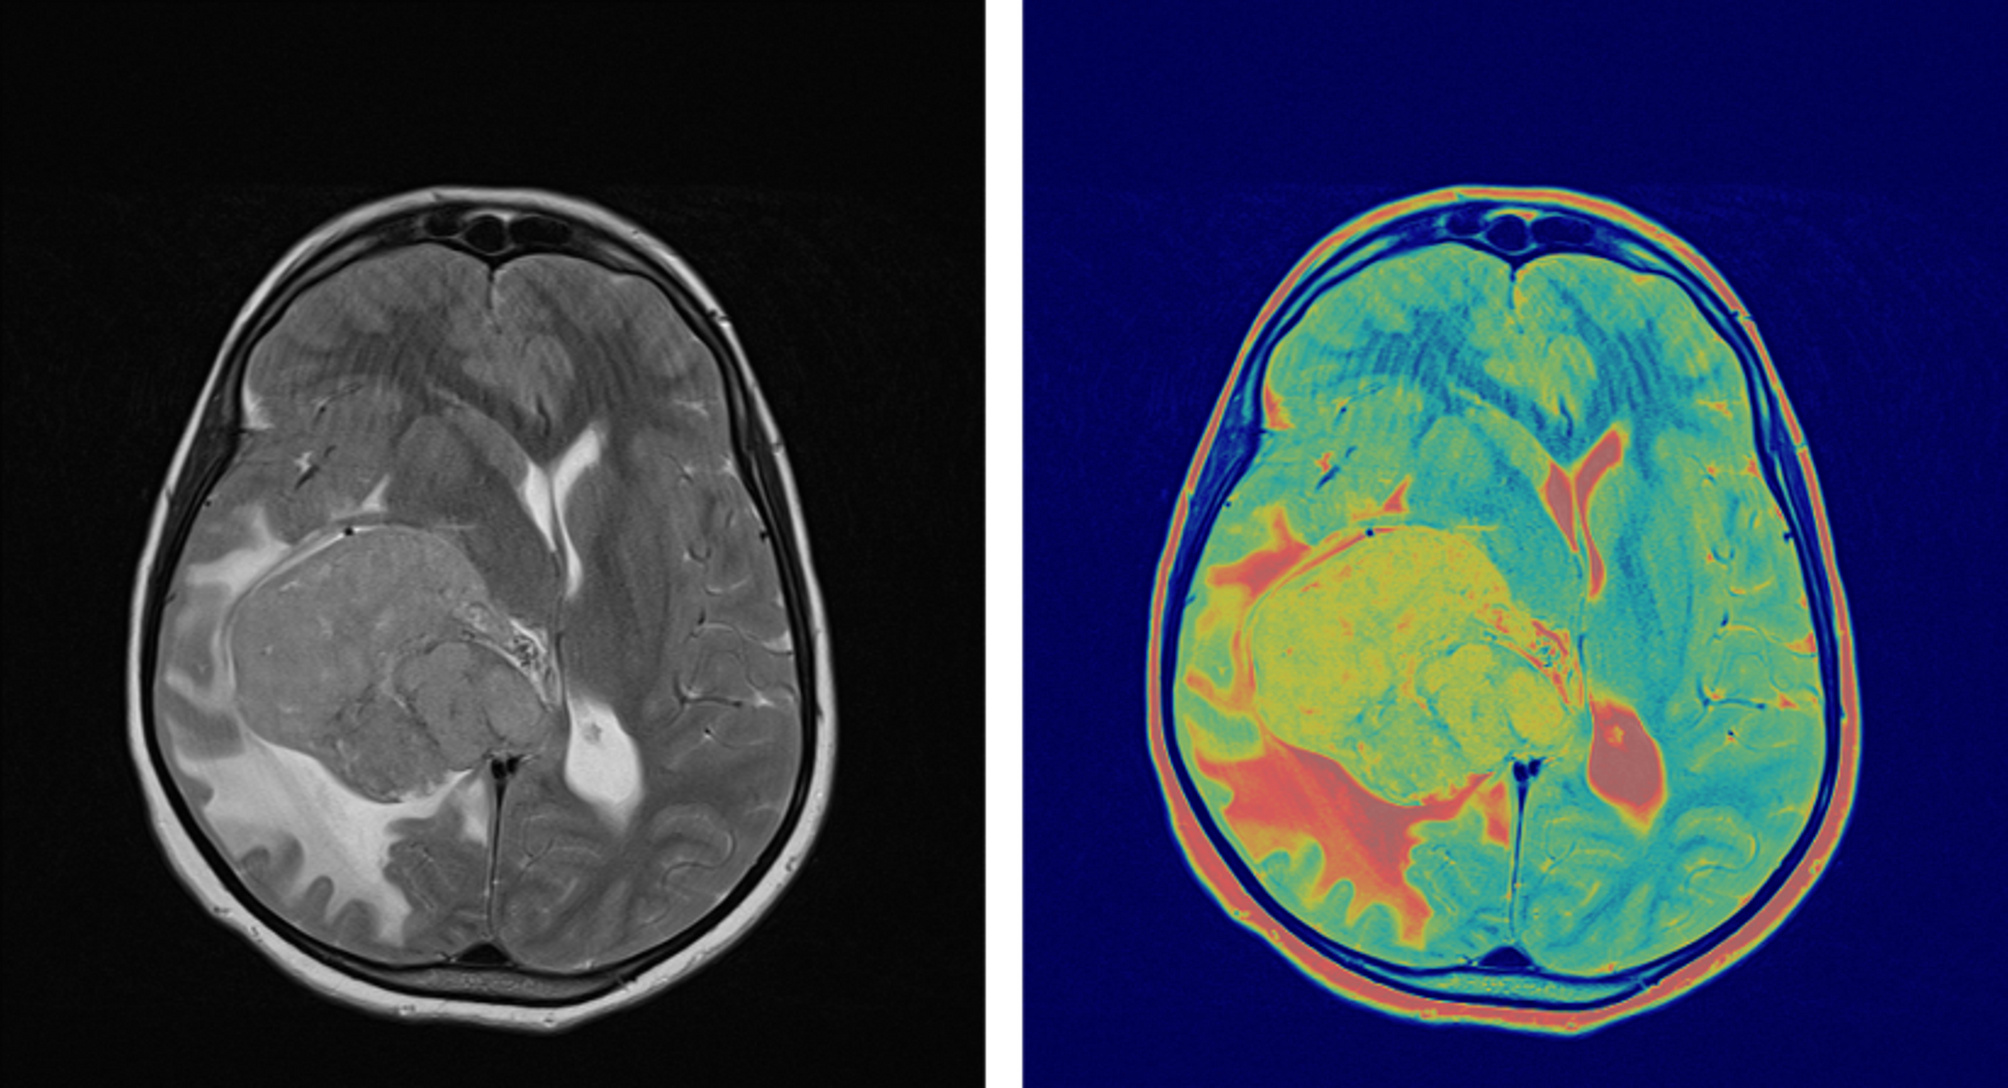

Pre-surgical FLT-PET/MRI brain imaging showing glioblastoma contrast enhancement on Gd-enhanced MRI and FLT-PET activity concentration. PET image was normalized to create a Gd-enhanced T1-weighted MRI matrix.